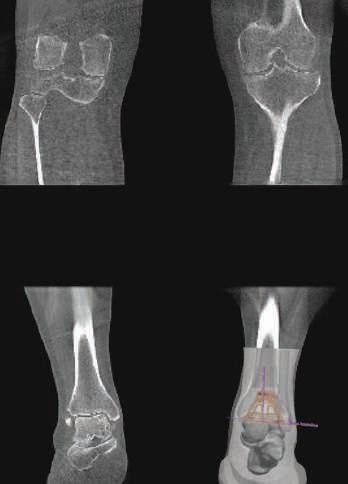

Small device foot print; 58”x73”; Point-of-Care; Ready to incorporate into small office setting.

Radiation dose is significantly lower than standard MDCT protocols1.

35% improved fracture detection and 2-fold improved identification of complex fracture over X-Ray2.

Self-shielded; Runs off standard 230V/30A outlet; 33-55 seconds per orbit.

Assess total leg alignment with 0.3mm slices.

Vendor approved protocols for joint replacement planning.

Decrease operative time and increase rates of implant survival.3